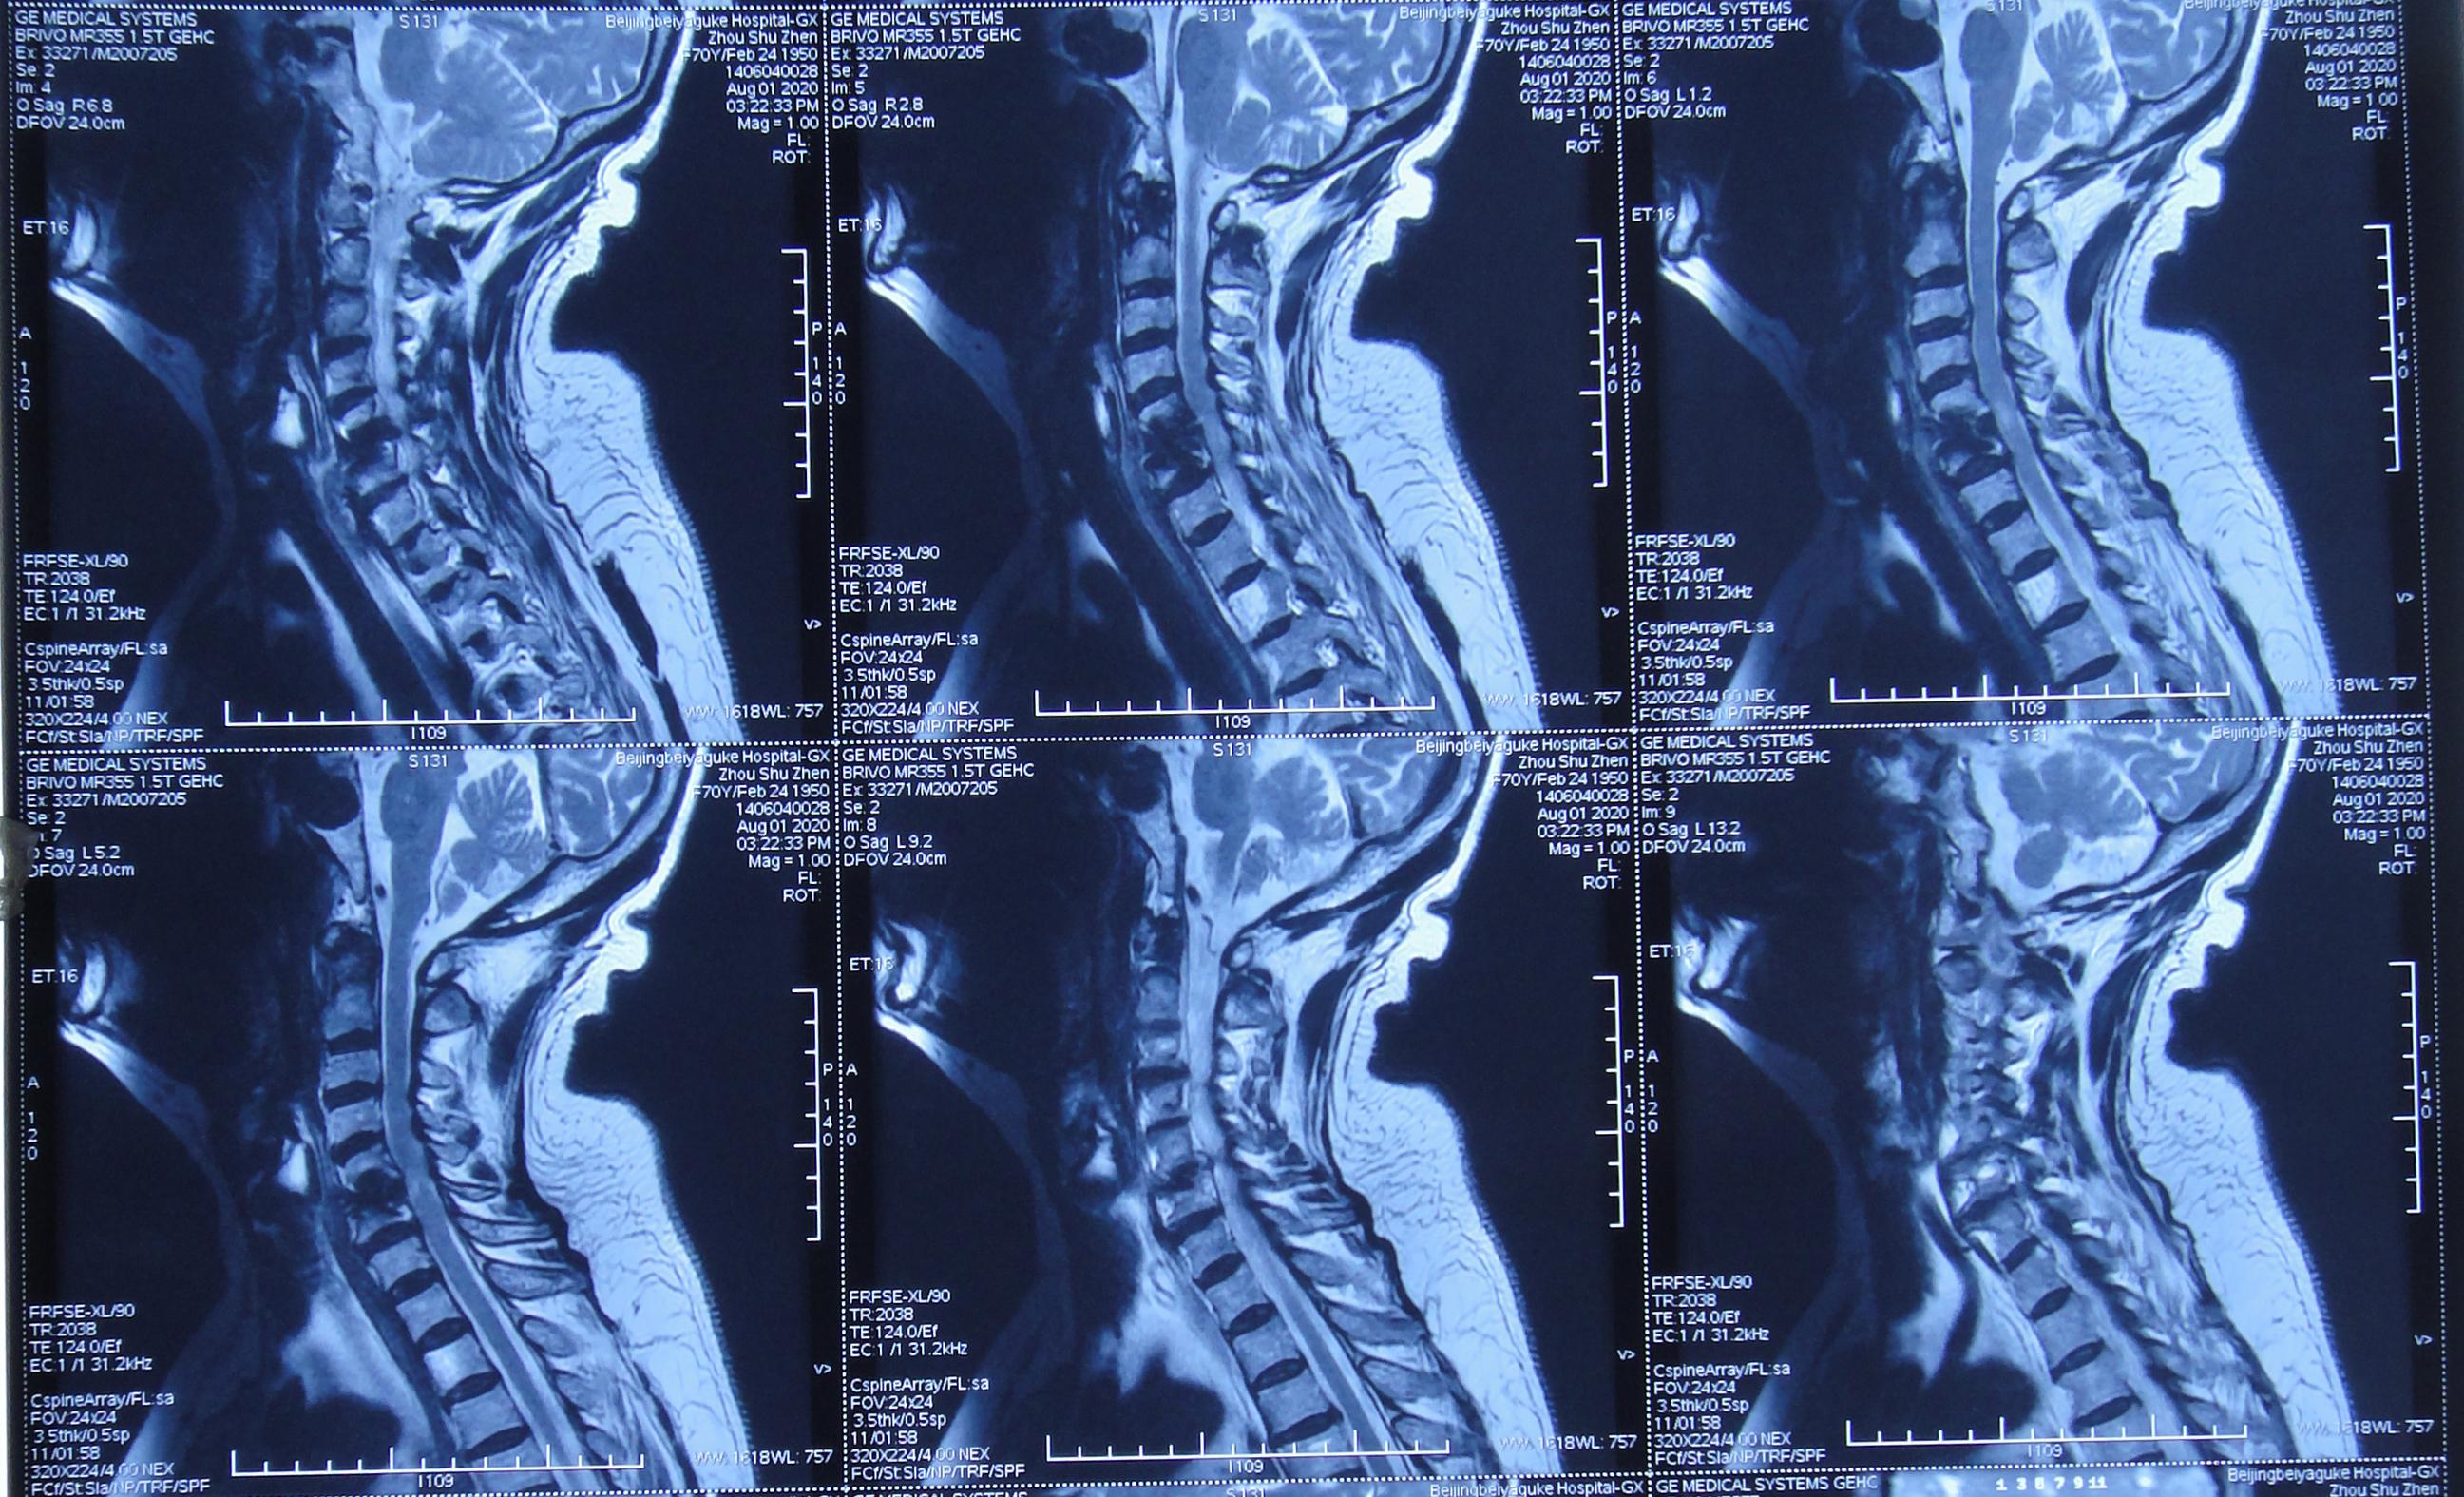

2020年8月1日(即第一次颈椎病术后第101天)患者复查颈椎MR示颈椎病,椎管狭窄,颈髓受压( 图-5 )。

图-5: 2020年8月1日颈椎MR

2020年8月4日(即第一次行前路颈5-6椎间盘切除椎间植骨融合内固定术后第114天),再次行颈椎前路颈5、颈6锥体次全切、人工锥体钛板螺钉内固定术,2020年8月5日(即第二次颈椎病术后第1天)复查颈椎平片及颈椎CT示椎管狭窄解除,人工椎体位置良好( 图-6、图-7 )。

图-6: 2020年8月5日颈椎平片

图-7: 2020年8月5日颈椎CT